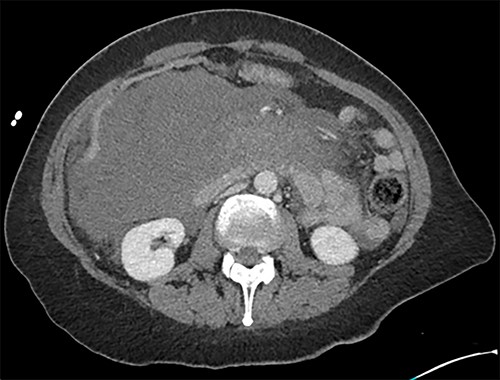

Initially, the main diagnosis considered was an aortic dissection. Other initial general surgical differentials were a perforated viscous or severe pancreatitis. Computed tomography (CT) angiogram showed a 6 mm pseudoaneurysm arising from a branch vessel 3 cm distal to the origin of the SMA. There was no active arterial blush; however, there was a large associated mesenteric haematoma (measuring 4.5 × 8.0 × 13 cm) with large volume haemoperitoneum (Figs 1–3). There was also a splenic artery aneurysm measuring 5 mm with no evidence of active haemorrhage. After the CT scan, she was noted to be haemodynamically unstable when lying supine, due to inferior vena cava compression by the mesenteric haematoma. A pillow was placed under her left lateral side to act as a wedge to reduce this. She proceeded to urgent angioembolization by interventional radiology, which confirmed the pseudoaneurysm on angiography (Fig. 4, left). The SMA was accessed and the aneurysm was successfully embolized with 3 mm diameter 15 cm length Ruby micro-soft detachable coil (Fig. 4, right).

Axial image of the large retroperitoneal haematoma in portal venous phase.